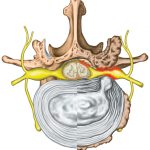

椎間板とは

椎間板は背骨のブロック状の24個の骨(椎骨)をつなぐもので、

23個あり、主に3つの役割を持っています。

1) 吸収

2) 動き

3) 神経の保護 (最も重要な機能)

椎間板の約85%が水分で、一日の変化により膨張したり、縮んだりします。

椎間板ヘルニアとは

椎間板ヘルニアとは、椎間板のもつ3つの機能が損なわれることで、

中心にある髄核が、はみ出てしまった状態を言います。

頚椎ヘルニアは椎間板の中にある髄核がはみ出した状態

のことをいいます。 はみ出した髄核は、神経根や脊髄を圧迫してさまざまな症状をおこし、